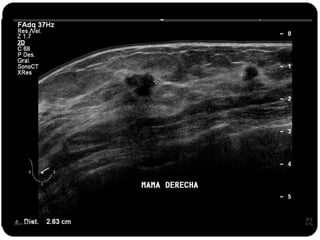

Paciente femenina de 66 años con historia clínica de 1er gesta antes de los 30 años y antecedentes de lactancia positiva, presenta una lesión palpable en la mama derecha. Los estudios radiológicos indican un diagnóstico de bi-rads 5, con biopsias revelando adenocarcinoma lobulillar infiltrante en la glándula mamaria derecha y adenocarcinoma ductal in situ en la izquierda. El caso fue evaluado por las doctoras Jacqueline Preciado Vargas y Beatriz E. González Ulloa.